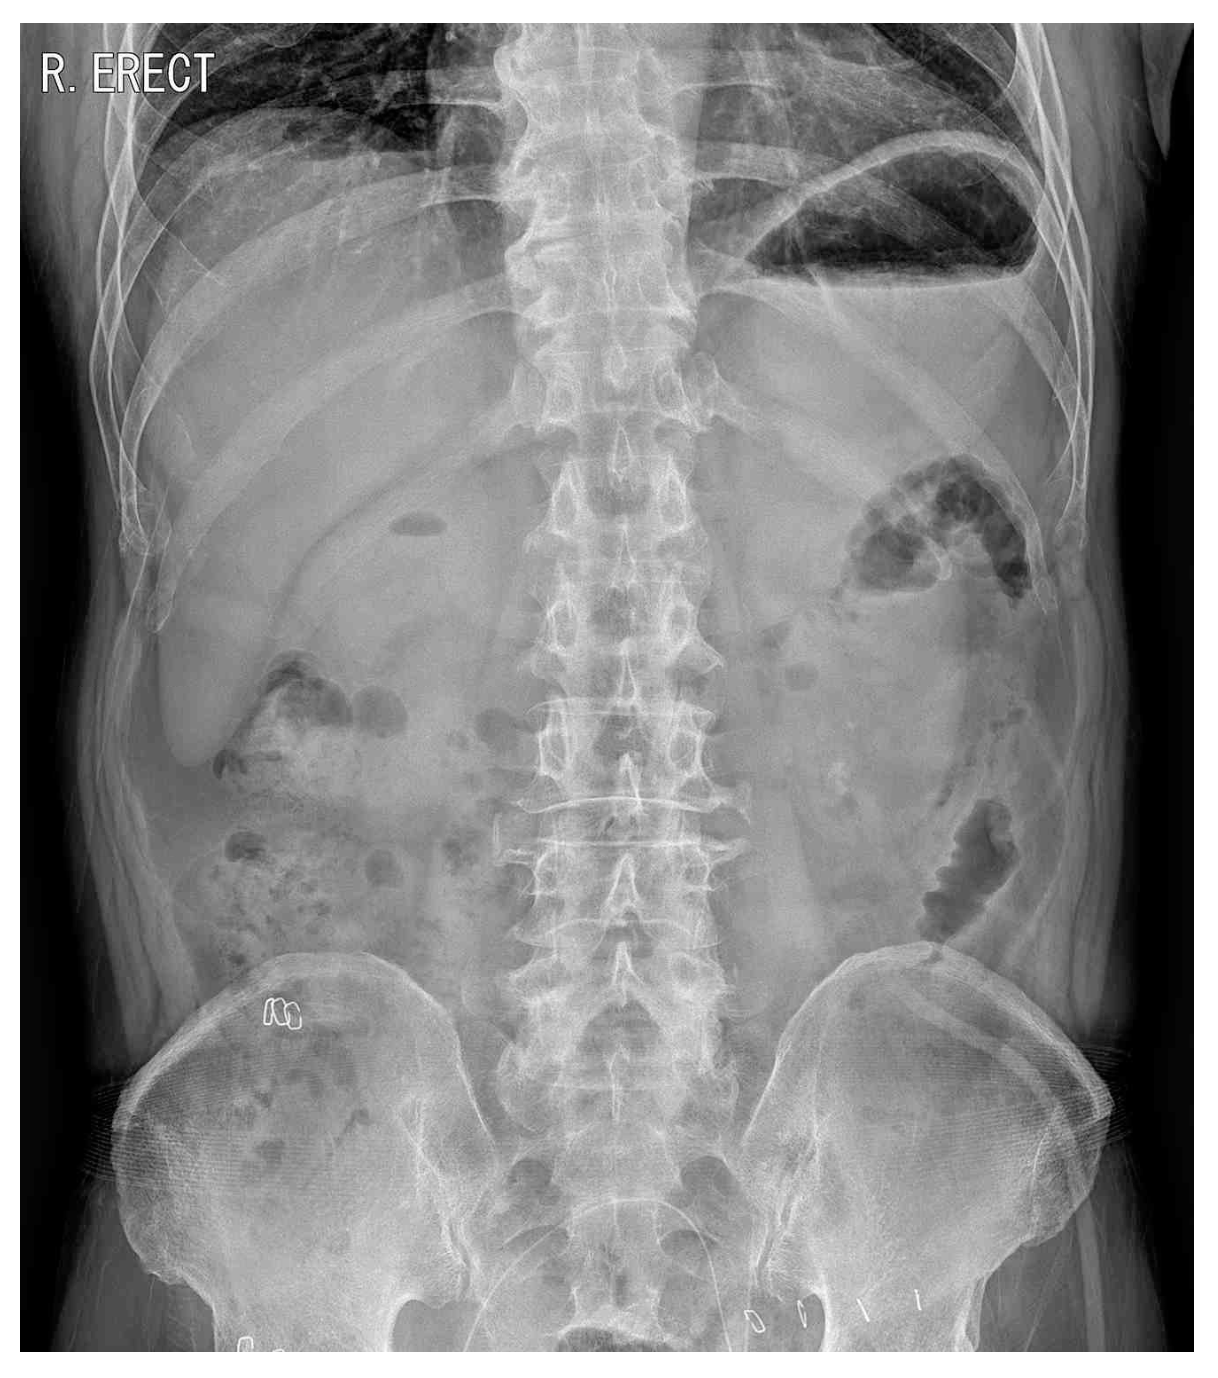

65세 남자가 구불결장암으로 복강경 전방절제를 받고 입원 중이다. 수술 후 5일째 아침부터 아랫배가 심하게 아프다고 한다. 통증은 2시간 전부터 시작되었고, 점점 더 심해진다고 한다. 혈압 90/55 mmHg, 맥박 105회/분, 호흡 24회/분, 체온 38.3°C이다. 배는 조금 불러있고 아랫배에 압통과 반동압통이 있다. 혈액검사 결과는 다음과 같다. 수술 후 4일째 복부 X선사진과 5일째 복부 X선사진이다. 처치는?

CXR (POD#5): Subdiaphragmatic free air

• 위장관 천공이 의심되는 경우 CXR을 통해 빠르게 천공 여부를 평가해야 한다. 수술 4일차에는 천공 소견이 없었으나, 증상이 시작된 5일차 흉부 X선 검사에서 횡격막 아래 공기가 관찰되었으며, 이는 수술 부위 천공과 이로 인한 범복막염을 강하게 시사한다.

• 압통, 반동압통 등 복막염 소견과 CXR에서 공기배증 소견이 확인되므로 이는 응급수술의 적응증에 해당하며, 응급수술을 통해 천공 부위를 교정하고 감염을 제어하여야 한다.

• 복강경 수술을 할 때는 시야 확보 등을 위해 복강 내 CO2 등의 가스를 주입하며, 따라서 수술 후에는 정상적으로 pneumoperitoneum이 관찰될 수 있다. 단, 본 증례는 수술로 인해 유입된 가스가 POD 4일차에 전부 흡수되었음이 확인된 이후 다시 POD 5일차에 pneumoperitoneum이 생긴 것이므로 이상 소견이 맞다.